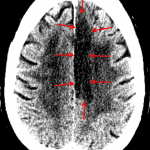

- Hypodensity and loss of gray-white differentiation involving the left paramedian frontal and parietal lobes

- Remote left basal ganglia lacunar infarct

- Sequela of chronic microvascular ischemic disease

- Left ACA territory infarct

Hypodensity and loss of gray-white differentiation involving the left paramedian frontal and parietal lobes consistent with acute/early subacute left ACA territory infarct. No significant associated mass effect or evidence of hemorrhagic conversion.

Remote left basal ganglia lacunar infarct.

Sequela of chronic microvascular ischemic disease.